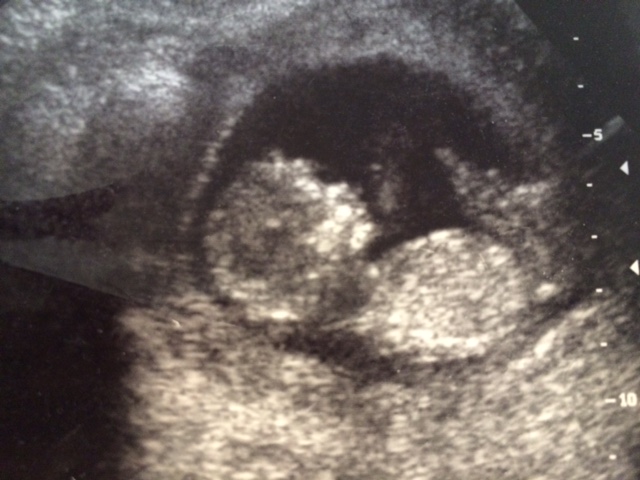

Hi, here's a transvaginal ultrasound from 13 weeks. Any guesses based on skull theory? Thanks!

I don't like the just for fun theories. Do you have any other pics where there might be a nub visible? I don't see one here.

Hi, I have this one from 7 weeks. It's transvaginal. Unfortunately don't have a clearer picture from 13 weeks that shows the 'nub'. Thanks for your reply!!